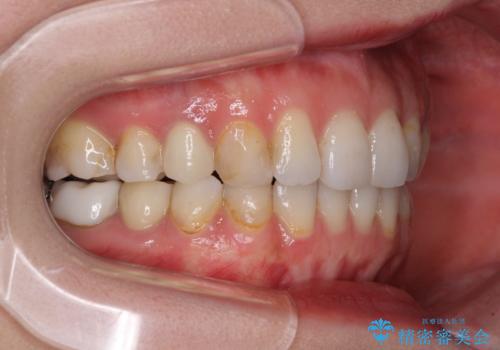

長時間のマウスピース装着と、患者様自身でのゴムかけに協力いただき、自然な口元に仕上げることができました。

気になっていた変色した歯もオールセラミッククラウンで本物の歯のようになり、患者様には大変満足していただきました。